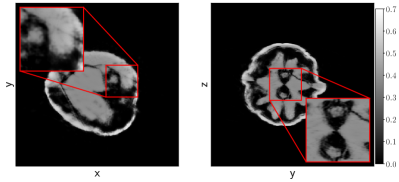

In Figure 7 we show the average and standard deviation of the TSE and the SSIM for the considered cases. We observe that U-net and MSD achieve the most accurate results and that NN-FDK and SIRT+ closely follow. The FDK algorithm is lowest in all categories. Between NN-FDK and SIRT+ we see that NN-FDK performs best for the noisy reconstruction problems and SIRT+ achieves better results for the reconstruction problems without noise. We visualize the noise for the lowest and highest in Figure 8 by showing a line profile through the center of the slice. Here we see that for the noisiest problems the amplitude of the noise can be as high as the maximum value of the phantom. In Figure 9 we show 2D slices of reconstructions of the test phantoms for the three types of reconstruction problems. In all cases we still observe reconstruction artifacts, but comparing these to the baseline FDK reconstructions, the majority is removed or suppressed.

Comparing the results to the simulated data experiments we see that SIRT+ performs worse on the experimental data, even with the additional regularization of early stopping. This is most likely due to the high-dose datasets still containing noise, whereas this is completely absent in the simulated data experiments. These differences are illustrated in Figure 10 where 2D slices of the reconstructions for the high-dose reconstruction problem with projection angles are shown.